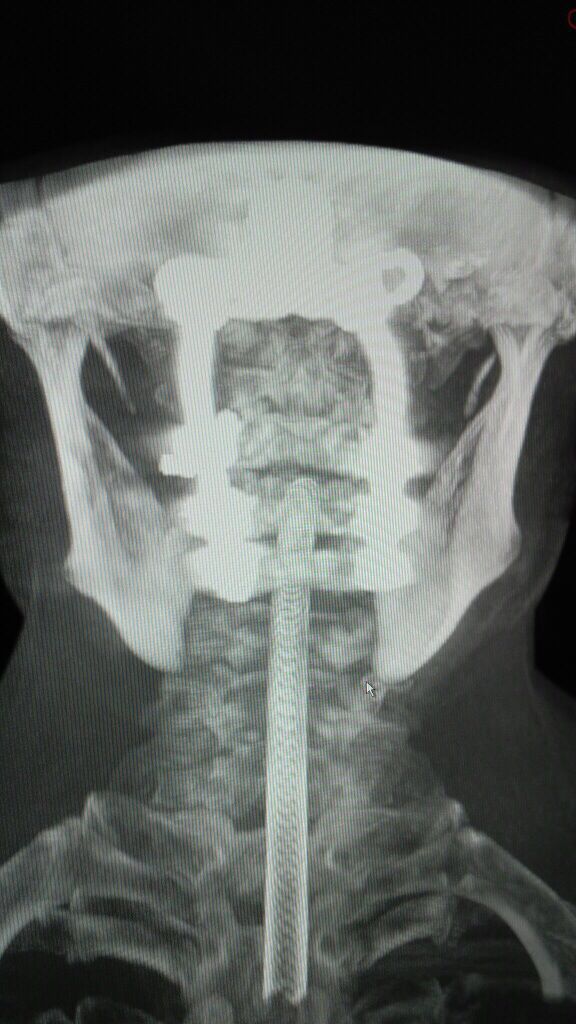

术中O-Arm确定固定位置良好: